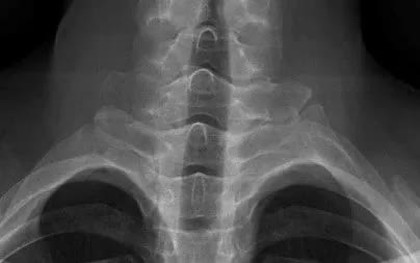

Đau cột sống cổ kéo dài ở người trẻ: Đừng chủ quan với viêm cột sống dính khớp

Một nam thanh niên 26 tuổi đau cột sống cổ suốt 5 tháng, điều trị nhiều nơi không khỏi, được chẩn đoán viêm cột sống dính khớp.